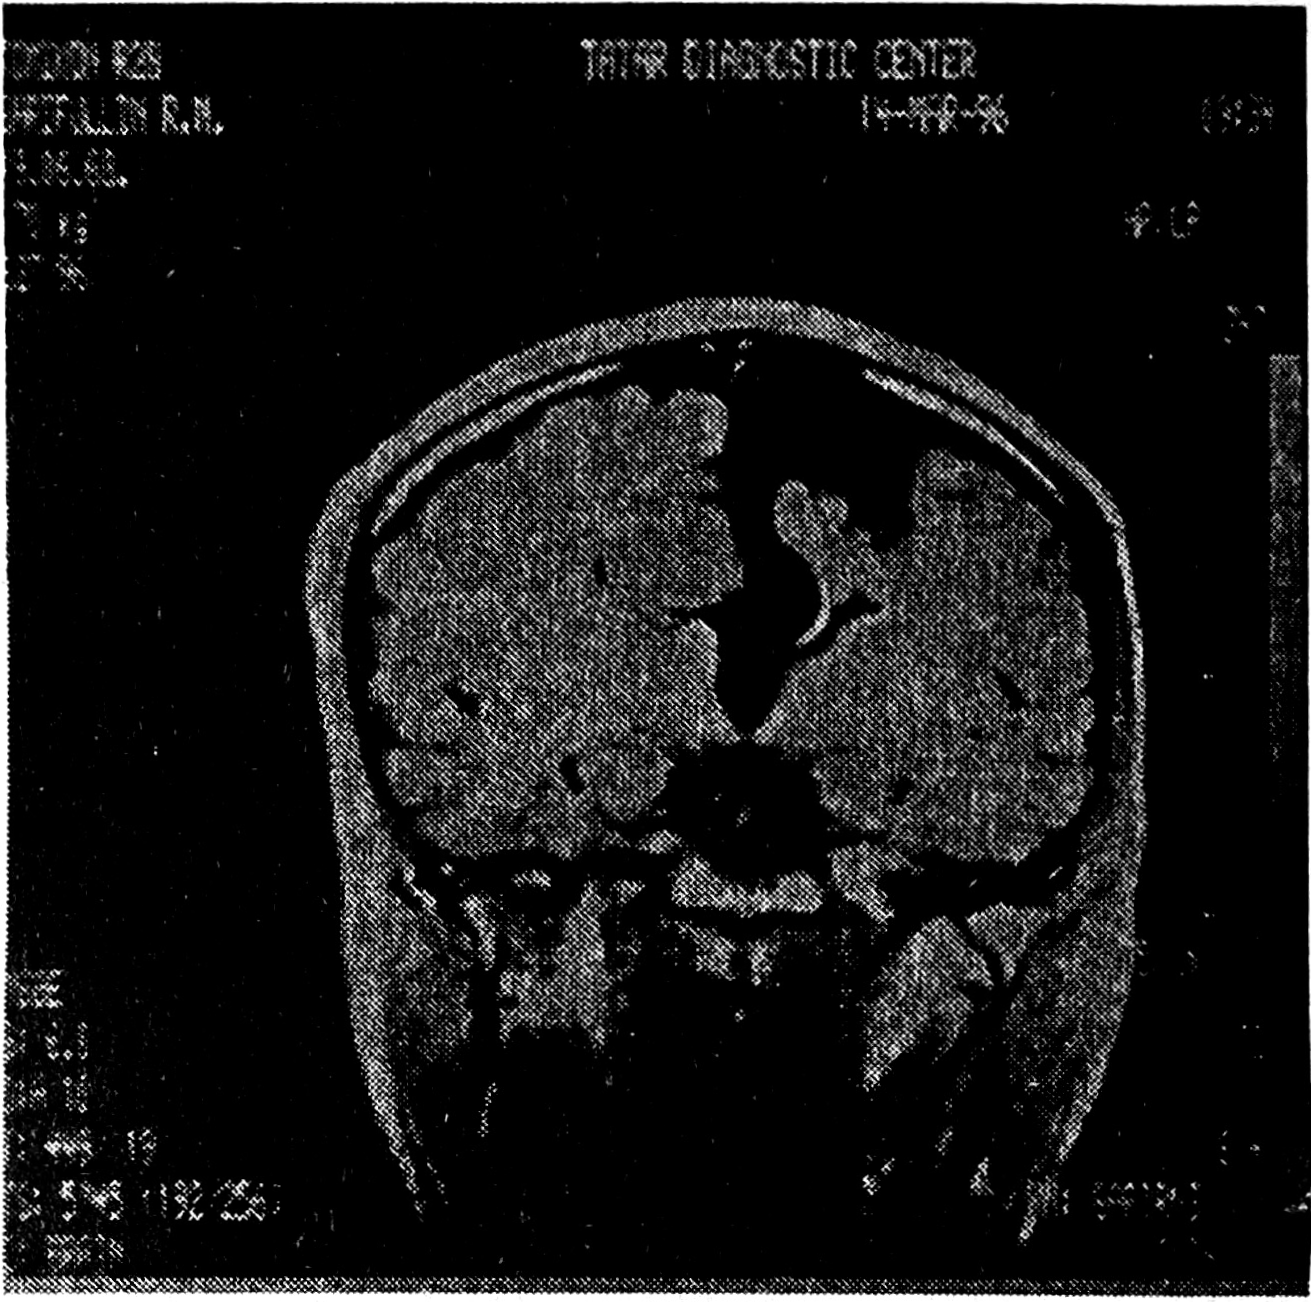

Рис. 2. ЯМР-томограмма арахноидальной кисты супра- и субтенториальной локализации (гипоплазия левого полушария головного мозга и мозжечка).

Клинико-неврологическая диагностика ВАК крайне затруднительна. Большинство обследованных больных на втяжении длительного отрезка времени лечились по поводу вегетососудистых дисфункций, гипертензионно-гидроцефальных синдромов неясной этиологии, стойких остаточных явлений после перенесенных нейроинфекций, травматической энцефалопатии. Псевдотуморозный тип развития заболевания (прогредиентный или прогредиентно-ремиттирующий), сочетание гидроцефально-гипертензионного синдрома с медленно прогрессирующей или стабильно существующей очаговой симптоматикой на фоне краниографически верифицируемых гидроцефальных изменений в виде истончения кости, ее дуальных деформаций, углублений основания черепа настораживают в отношении возможности ВАК и определяют необходимость использования визуальных методов обследования мозга [3, 4]. Наиболее убедительные данные могут быть получены в результате выполнения ЯМР- и КТ-томографий, причем первый из упомянутых методов является наиболее информативным. Возможность получения ЯМР-томограмм практически в любой из желаемых плоскостей существенно расширяет разрешающую способность метода и позволяет с его помощью дифференцировать ВАК и кисты другой природы.